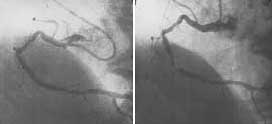

관상동맥 중자술을 통해 좁아졌던 혈관 내경을 넓힐 수 있다. 사진은 수술 전(왼쪽)과 수술 후의 모습.

대기업 중역인 안모씨(52)는 최근 회사에서 받은 건강검진 결과에서 가벼운 고혈압과 심전도 이상 소견이 나오자 얼굴이 새파랗게 질렸다. 4년 전 큰형이 쉰아홉의 나이에 심장마비로 비명횡사한 데다, 둘째 형도 지난해 심장혈관의 심한 협착으로 수술을 받은 전력이 있었기 때문. 안씨가 더욱 놀란 것은 이런 가족력에 대비, 10년 전부터 담배도 끊고 운동도 하는 등 나름대로 건강관리를 해온 상황에서 이런 결과가 나왔다는 사실이다. 결국 안씨는 관동맥 조영술을 받은 결과 혈관 두 곳에 심한 협착이 있는 것으로 드러나 좁아진 혈관을 넓히는 수술을 받아야 했다. 평소 운동을 하던 중 느낀 가슴 압박감도 심혈관계 질환에서 비롯된 것이었다.